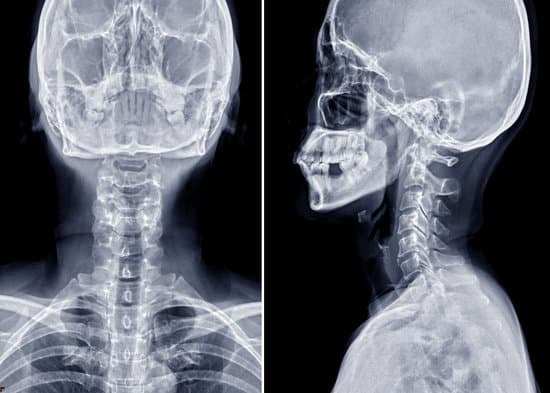

경추 디스크 X-ray (방사선 검사): 목적과 절차

X-ray(방사선 검사)는 디스크 자체를 직접 확인할 수는 없지만, 뼈의 정렬과 상태를 파악해 경추 문제를 추정하는 데 중요한 역할을 합니다. 특히, 목 통증의 원인을 파악하고 치료 계획을 수립하는 초기 검사로 활용됩니다.

정면 및 측면 촬영

정면 촬영: 목뼈의 좌우 정렬 상태와 척추 사이 간격을 확인합니다.

측면 촬영: 목의 전만(정상 곡선)과 척추 간의 높이를 평가합니다.